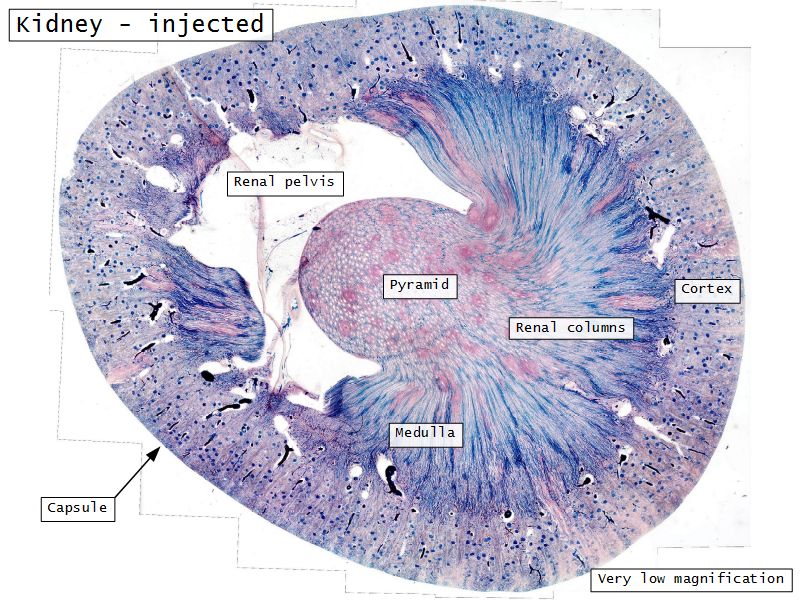

Kidney

- Capsule

- Cortex

- Medulla

- Multilobar

Multilobar

- Conical mass (pyramid)

- Medullary tissue

- capped with

- Cortex

- Delineated by

- Renal columns

- Apex of pyramid

- Papilla

- Projects into renal pelvis

Capsule

- Irregular dense CT

- Surrounded adipose tissue

- Make an annotated drawing of the macroscopic view of the kidney.